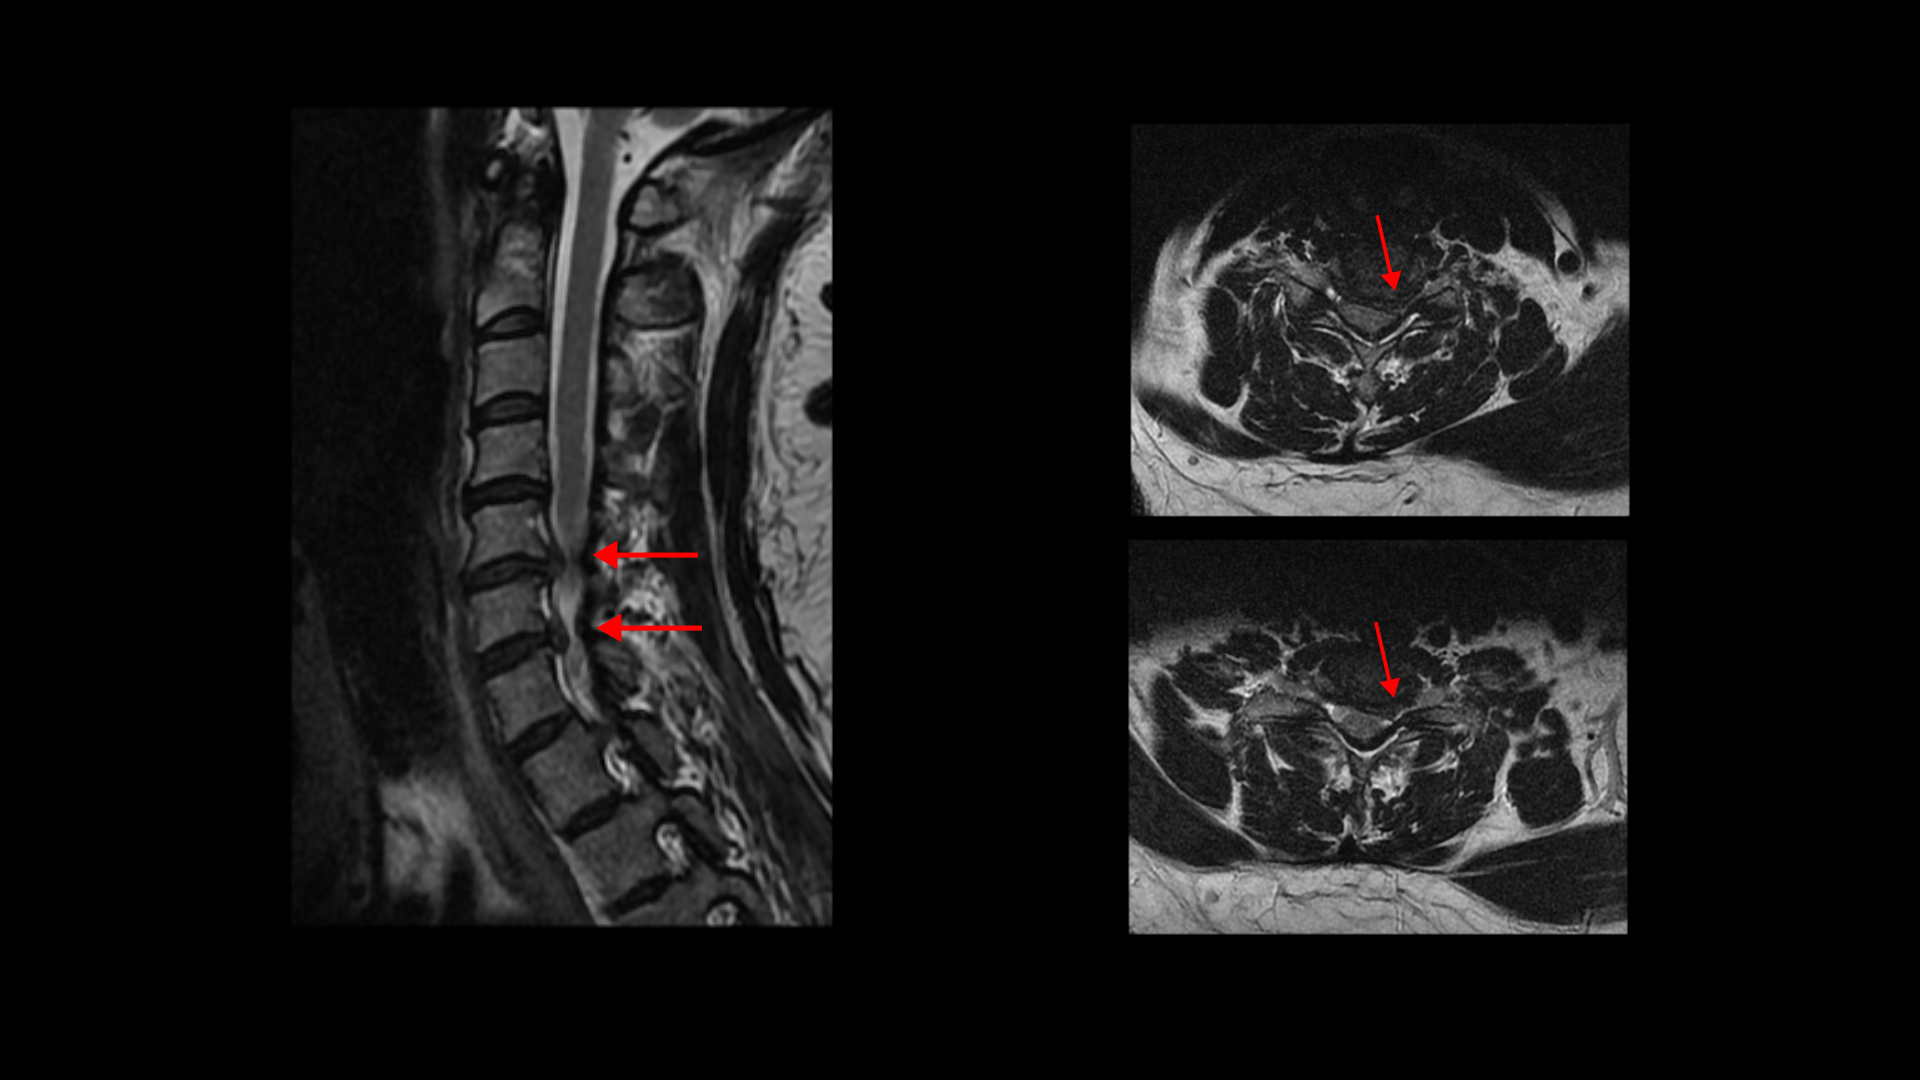

이분 MRI를 보면 목디스크 5번 6번과

6번 7번 두 마디가 왼쪽으로 심하게 밀려 나와 있습니다.

이렇게 심하게 밀려 나와 있으니까 왼쪽 팔의 통증과 함께 마비도 있고 앉거나 일어서면 목의 커브가 조금씩 변하면서 신경을 더 눌러, 앉기도 서서 걷기도 어려운 겁니다.